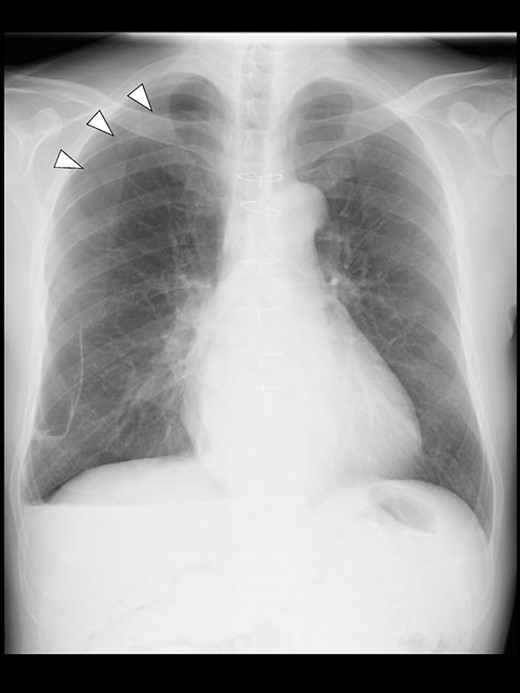

A 57-year-old male, 178 cm and 69 kg, was scheduled for a laparoscopic appendectomy for chronic appendicitis. The patient had undergone mitral valve repair for infective endocarditis via a median sternotomy 16 years before and minimally invasive esophagectomy (MIE) with intrathoracic anastomosis using a gastric tube for esophageal cancer 5 years before. Preoperative tests, including a chest radiograph (Fig. 1), were unremarkable. The computed tomography (CT) revealed no emphysematous lung cyst. Anesthesia was induced with intravenous remifentanil (0.3 μg/kg/min) and propofol (100 mg). Intravenous rocuronium (50 mg) was administered to facilitate tracheal intubation. Anesthesia was maintained with inhaled sevoflurane (1.5%) and intravenous remifentanil (0.1–0.3 μg/kg/min). The lungs were ventilated with a volume-guarantee pressure-controlled mode employing an inspired oxygen concentration of 35%. Percutaneous arterial oxygen saturation (SpO2) was maintained at 96%–100%. In addition to local anesthetic wound infiltration, intravenous fentanyl (300 μg) and acetaminophen (1000 mg) were administered for immediate postoperative analgesia. Operation and anesthesia times were 121 and 156 min, respectively. The infusion volume was 1350 ml. Emergences from anesthesia and extubation were uneventful. SpO2 in the postanesthesia care unit was maintained above 95% without supplemental oxygen. The patient did not complain of chest pain or dyspnea.